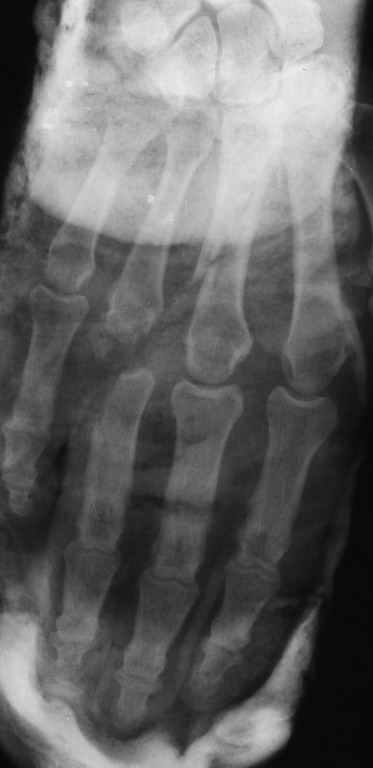

Диагноз на 15.07.05: Стойкая смешанная дермотеногенная контрактура 3,4 пальца правой кисти 3 степени.

-- удалить спицы;

-- сделать рентгенограмму;

Диагноз: Стойкая Смешанная дермотеногенная контрактура 3,4 пальца правой кисти.

Судя по выписному эпикризу, рентгенограммам и фотографиям, пациенту

показано этапное лечение.